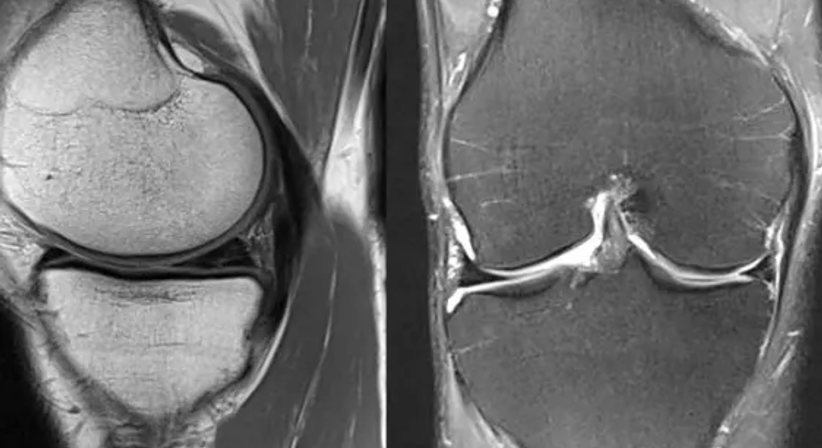

Die Arthroskopie wird für Diagnose und Therapie eingesetzt und findet am häufigsten bei Meniskus- und Knorpelschäden am Kniegelenk ihren Einsatz. Die Gelenkspiegelung erfolgt mithilfe eines sogenannten Arthroskops, das über einen kleinen Hautschnitt in das Gelenk eingeführt wird. Dadurch kann das Innere des Gelenks in Echtzeit untersucht und gegebenenfalls chirurgisch therapiert werden.

Liegt ein Meniskusriss vor, wird dieser, je nach Rissart, Begleitpathologien und Alter des Patienten, entfernt oder genäht. Im Falle von Knorpelschäden kann mitunter mittels Mikrofrakturierung eine Verbesserung der Knorpelregeneration erreicht werden.